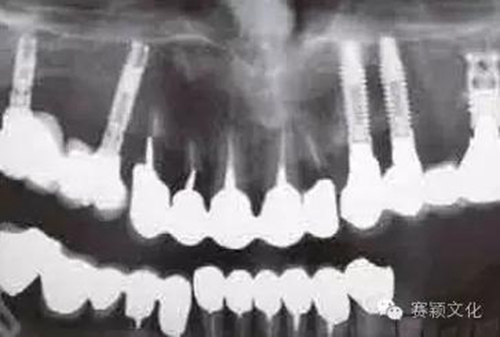

2.jpg

圖2 術(shù)前全景片